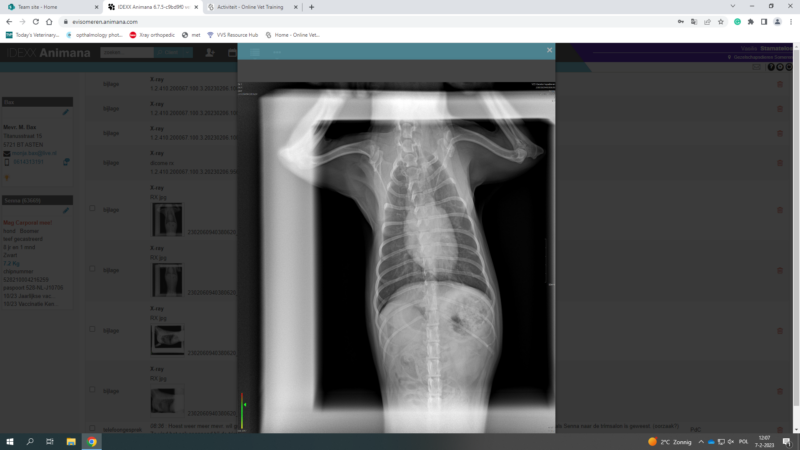

Chronic Cough problem with underline heart disease?

Hello again to the team,

i upload this post in order to discuss one of my cases with you

Its about a yorkshire terrier, 3 years old, female, sterilised, that has coughing problems for 6 months. According with the owner, the problem didnt start 6 months ago, but earlier. But the last 6 months is really getting worse. Before it was once per week…